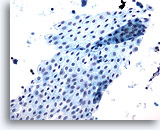

Figure 13

Peritoneal wash: Benign. 20X

Figure 13

Peritoneal wash:

Benign.

20X

For peritoneal washings the surgeon performs an irrigation or barbitage to collect cells for analysis. Pelvic mesothelial cells may be shed in broad and flat sheets. Sometimes the sheets fold so that overlapping of cells is evident. The benign nature of these mesothelial cells is obvious by their uniform arrangement and appearance.